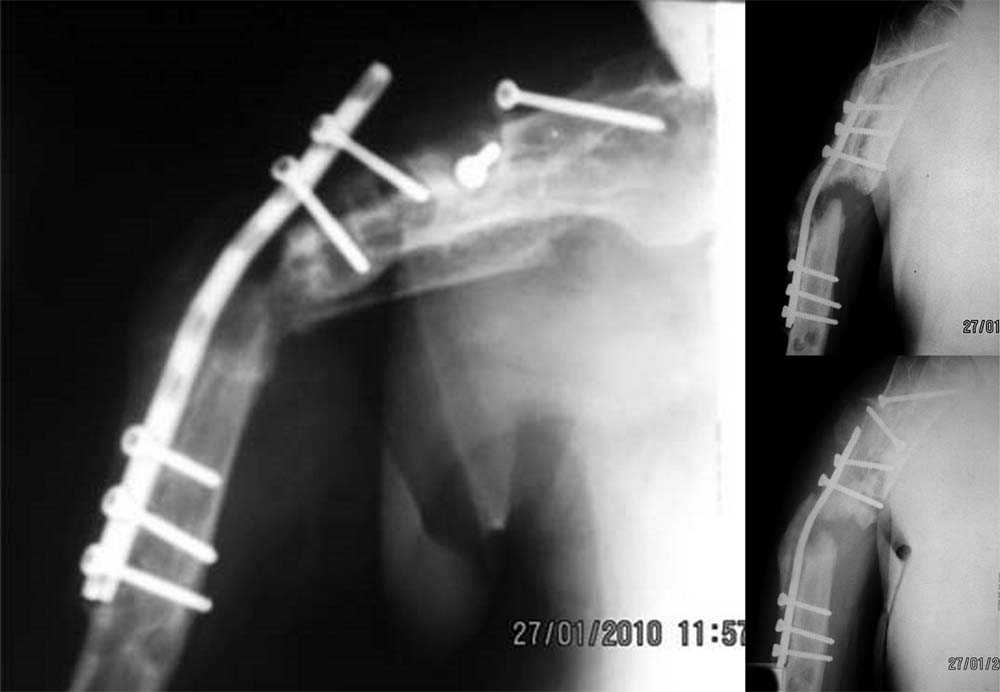

Уважаемый коллега! Судя по ренгенограммам, потенциал для сращения у данного перелома имеется. Основная проблема, ИМХО, заключается в отсутствии стабильной фиксации. В тоже время мягкие ткани достаточно скомпроментированы мредшествующими вмещательствами. Учитывая имющиеся ограничения (технические, финансовые)представляется логичным выполнить по возможности малотравматичное удаление металлокоснтрукции с последующей фиксацией аппаратом в режиме компрессии.

Мысли направляются в сторону минимально инвазивного удаления всего металла, закрытого формирования канала и остеосинтеза гвоздем с антибактериальным цементным покрытием. Чтобы это был своего рода

эндопротез диафиза.